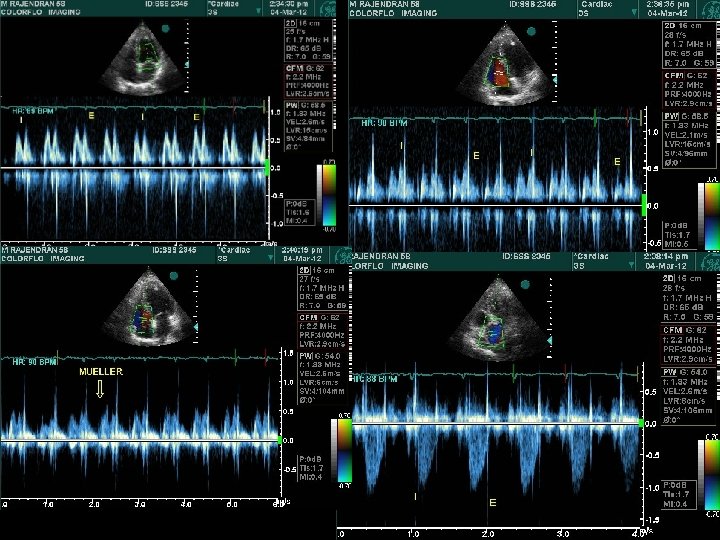

Abrupt standing • S 2 split which may be wide, may narrow down , while the fixed split may persist • A 2 OS interval widens – differentiates from wide split of S 2 • All murmurs ( except MVP/HOCM) decrease • ESM of HOCM becomes louder and longer • Click occurs earlier, murmur becomes longer in MVP – loudness shows variable response

Squatting • Increased venous return and CO > augments most murmurs atleast initially (AS, PS, MR, AR, VSD) Right heart murmurs do so earlier • Increased ventricular volume > murmur of HOCM ↓ murmur of MVP ↓→ • Ejection murmur of TOF ↑

Hemodynamics of Squatting T Murakami AHJ 2002; 15: 986– 988

T Murakami AHJ 2002; 15: 986– 988